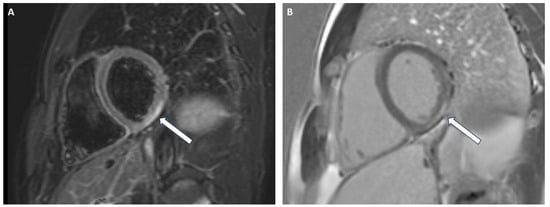

3.4. Hypertrophic Cardiomyopathy (HCM)

3.5. Fabry Disease